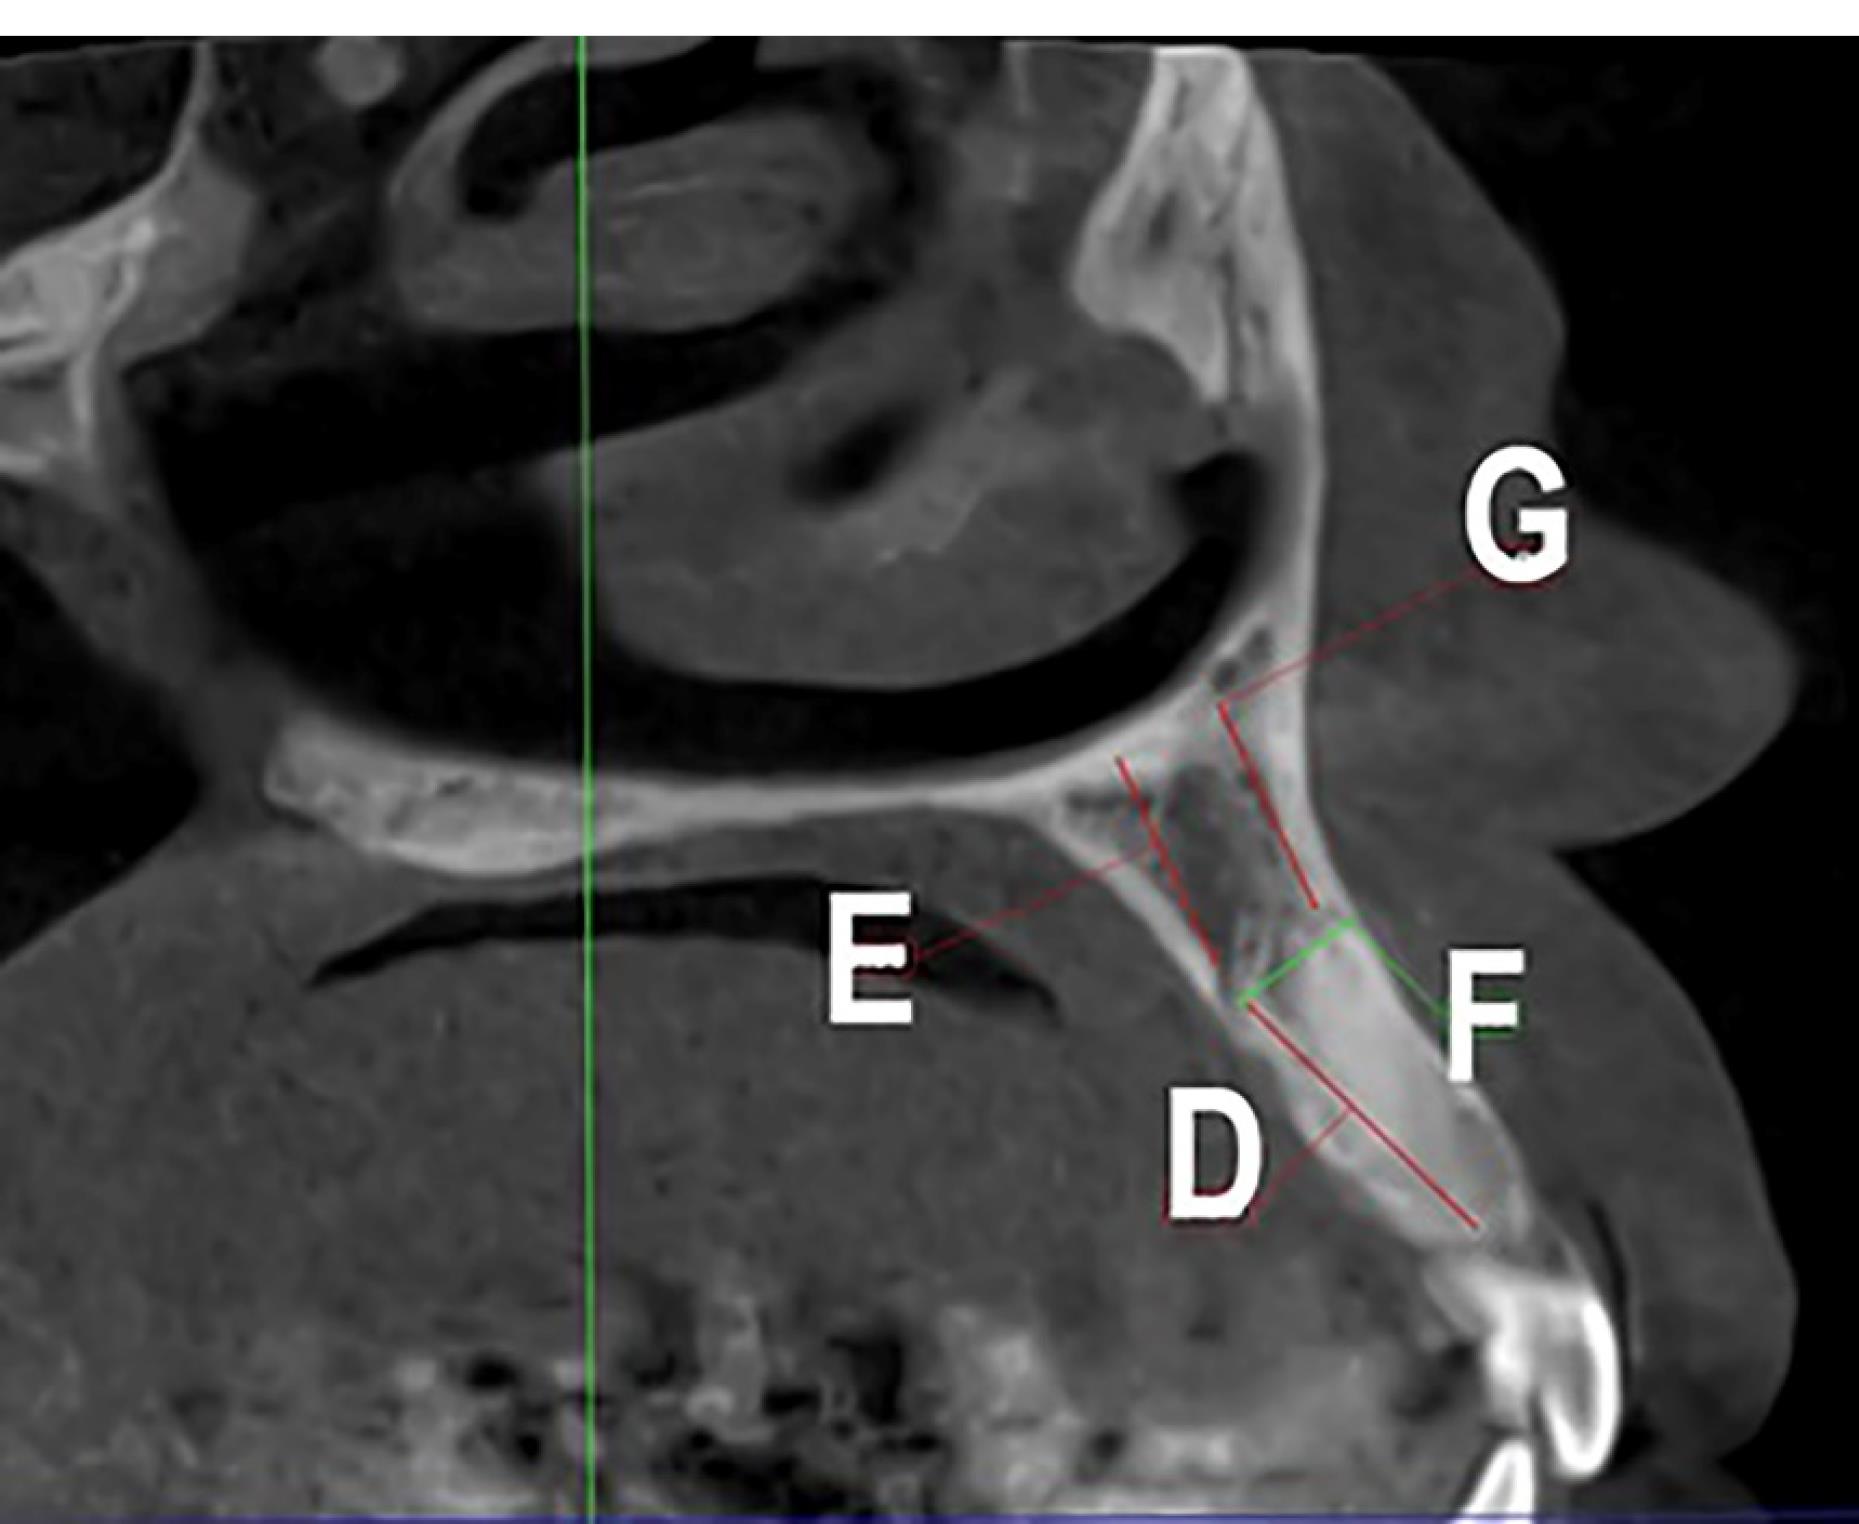

Figure 2.

Linear measurements made in the axial plane: A, the CS diameter; B, the CS distance from the perpendicular to the nasopalatine canal; C, the CS distance from the distal tooth; D, the CS distance from the main tooth; E, the CS distance from the mesial toot